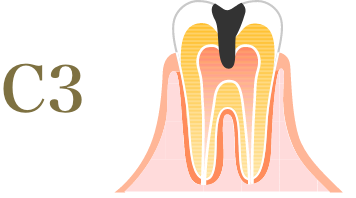

むし歯の進行度と治療方法

-

熱いものがしみ、ズキズキと

痛みを感じる状態に。- 治療方法

- 神経を処理する根管治療を行う